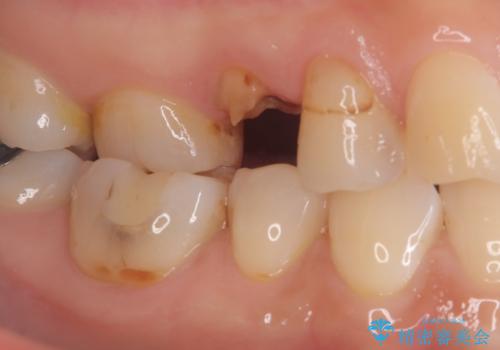

歯が取れた症例に対するセラミッククラウンによる修復

- 患者様は「歯が取れたこと」を主訴に来院されました。

診査の結果、土台ごと脱離しており、歯質の残存量も少ない状態でした。